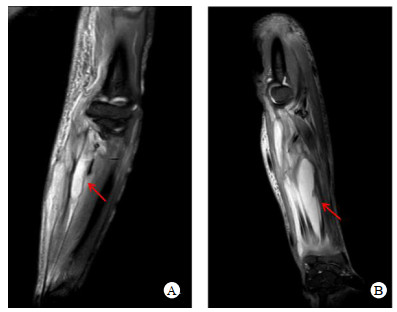

| 图A1、A2为12月16日(入院时)胸部CT:双肺多发小脓肿,右侧叶间裂积液,右侧胸腔积液;图B1、B2为1月6日胸部CT:双肺渗出较前加重,右侧包裹性胸腔积液;图C1、C2为1月25日(出院时)胸部CT:肺部感染明显吸收;病变如箭头所示 图 1 患者胸部CT图像 |

2021年1月4日转入急诊内科,追问病史,患者入院前2周右侧阴囊区疼痛,未诊疗,查超声:右侧附睾尾可探及一1.9 cm×1.4 cm大小混合回声,考虑炎症改变,继续青霉素+利奈唑胺抗感染。至1月6日仍持续低热,查体发现患者双侧上臂、前臂、双侧大腿、左侧小腿多发质硬条索状包块,皮温高。肌肉核磁示双侧上臂、前臂肌群肿胀渗出,考虑感染性病变并脓肿形成(图 2),复查胸部CT较前加重(图 1B1、B2)。行超声引导下肌肉脓肿穿刺、胸腔穿刺引流,穿刺液培养结果均阴性。现阶段肾功能恢复,将抗生素更换为青霉素240万单位q4 h+万古霉素1 g q12 h。1月13日患者再次出现高热,体温39.2 ℃,抽取血培养阴性,复查白细胞27.96×109/L,中性粒细胞比率0.90,降钙素原7.60 ng/mL,1, 3-β-D葡聚糖检测、半乳糖甘露醇聚糖抗原检测阴性,万古霉素血药浓度15.8 μg/mL,多学科讨论后给予达托霉素0.5 g q12 h抗感染治疗,因达托霉素不用于肺炎的治疗,故联用利奈唑胺600 mg q12 h,后患者症状逐渐缓解,再无发热,感染指标逐渐降至正常,肌力恢复,复查胸部CT好转(图 1C1、C2),于1月27日顺利出院。出院前为系统评估病情,行正电子发射计算机断层扫描检查:双肩及左肩胛旁、右髂翼至股骨小转子旁软组织肿胀并条片状低密度影,双侧髂内肌、臀部、大腿上段皮下软组织代谢增高,以上均考虑炎性病变,右臀部至大腿上端脓肿形成;双肺多发小结节/条片及絮状影,代谢不等增高,结合过往CT结果考虑炎性病变;右侧附睾局部代谢不均匀增高,多考虑炎性摄取。出院诊断:肺脓肿、脓胸、肌肉多发脓肿、肾周感染、附睾脓肿、感染性多脏器功能障碍综合征、感染性休克、急性呼吸衰竭、急性肾损伤、急性肝损伤、横纹肌溶解。出院后口服利奈唑胺1个月,3月2日、4月15日分别于本科复查,四肢脓肿、肺脓肿吸收,附睾脓肿较前缩小。